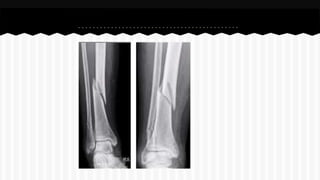

RESPONDA O NOME DO OSSO EM QUE

SE ENCONTRA A (S) FRATURA (A).